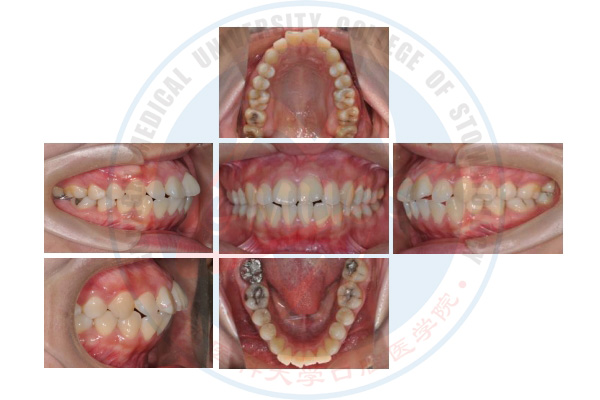

正畸治疗前

正畸治疗中

正畸治疗后